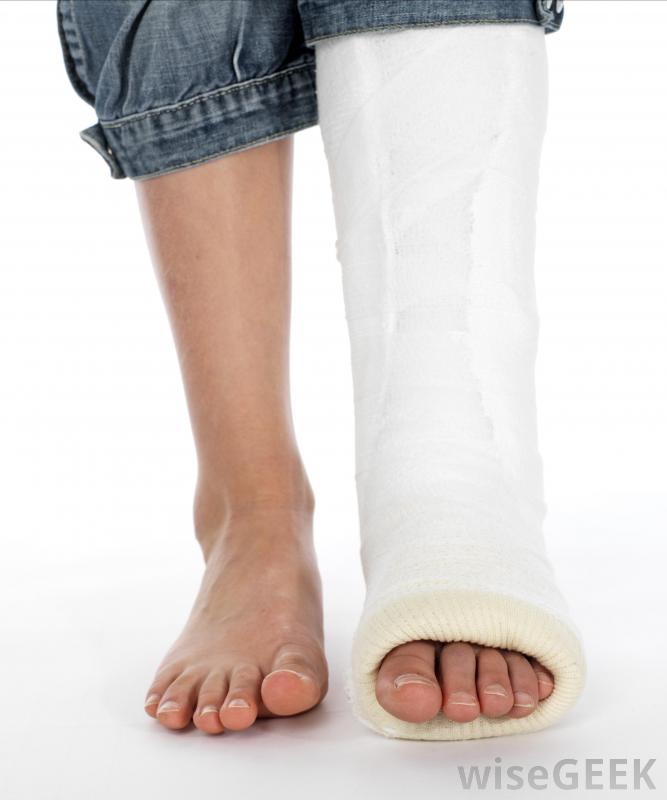

腓骨手术后,腿通常被固定在石膏中另一个可能出现在腓骨周围的问题是神经卡压,这可能导致刺痛感、疼痛或无法控制脚神经外科医生可能会建议腓骨手术来释放被困的神经并重新定位,这样患者就不太可能再次出现这种问题。其他的手术可以解决诸如:受伤后腓骨周围韧带撕裂;骨骼形状异常;或关节炎和感染引起的损伤